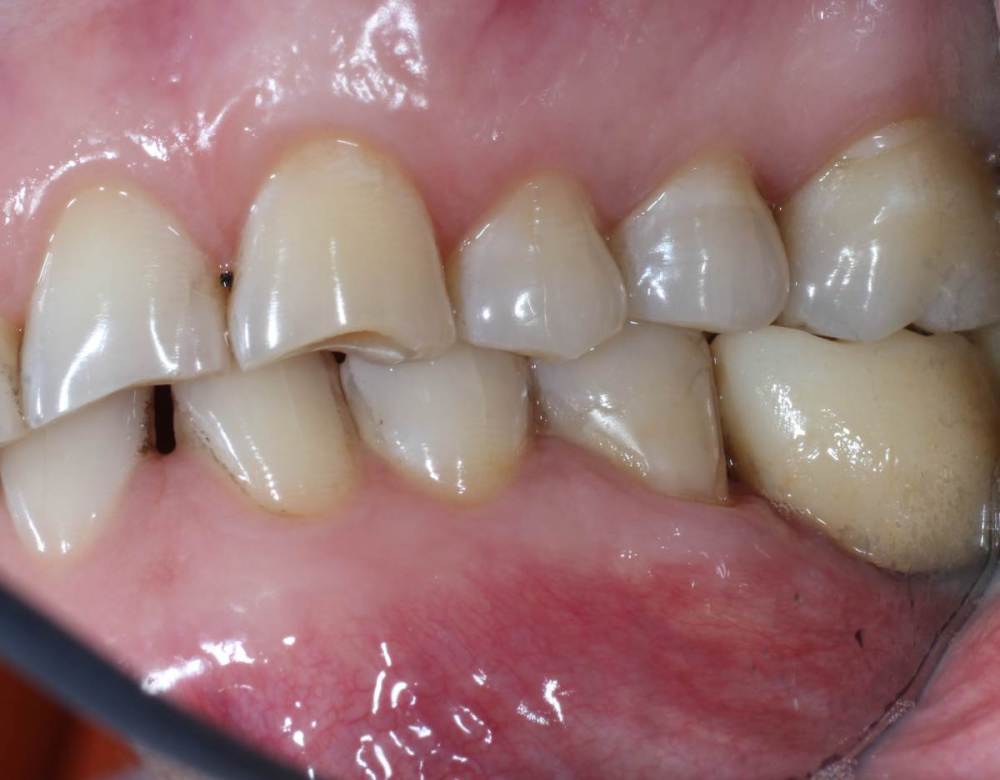

kuziy12 Опубликовано 2 ноября, 2020 Поделиться Опубликовано 2 ноября, 2020 Имплантация с синус лифтингом. Беда с позицией 2.3. Коронки на cad\cam, наносил розовую керамику и красил все сам. Сваливать не на кого) До: После имплантации: Формики: Десна: Постоянная конструкция: Улыбка: 3 Ссылка на комментарий

kuziy12 Опубликовано 9 октября, 2021 Автор Поделиться Опубликовано 9 октября, 2021 Дабы не плодить темы, выложу тут. Докрутил пациента полностью)) Ортопедия тоже моя. От переустановки импланта в области клыка отказалась. Ссылка на комментарий

Карен Аванесов Опубликовано 11 октября, 2021 Поделиться Опубликовано 11 октября, 2021 Ну вот, поздравляю Вас, получили благословение от Большого Зеленого, таперча работе служить 10 лет не меньше. 16 часов назад, Большой Зеленый сказал: Проблемы будут обязательно... а меня стертый клык насторожил, а работа жить будет, во рту чисто. 1 Ссылка на комментарий

kuziy12 Опубликовано 12 октября, 2021 Автор Поделиться Опубликовано 12 октября, 2021 11.10.2021 в 05:28, Большой Зеленый сказал: Проблемы будут обязательно... Спасибо за подсказку, а я думал вы уже потерялись где-то, давно вас на форуме не видно 22 часа назад, Карен Аванесов сказал: Ну вот, поздравляю Вас, получили благословение от Большого Зеленого, таперча работе служить 10 лет не меньше. а меня стертый клык насторожил, а работа жить будет, во рту чисто. с суставом проблемы, пац заниматься не хочет Ссылка на комментарий